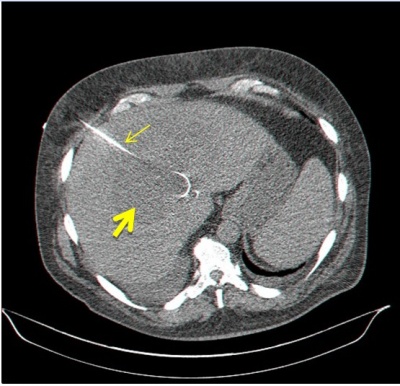

שיטה שמרנית יחסית היא הטיפול בעזרת דיקור מחטי של המורסה, כאשר הדיקור מוכוון על-ידי אולטרה-סאונד או טומוגרפיה ממוחשבת. מבצעים שאיבה של המורסה ולאחר מכן מכניסים נקז קבוע דרך מהלך המחט ויוצרים ניקוז חיצוני קבוע של המורסה (תצלום 41.10). שיטה זו הוכיחה את עצמה, והיא שיטת הבחירה לטיפול במורסה בכבד. את הנקז המוחדר למורסה יש לשטוף פעמים ביום במטרה למנוע סתימה של הצנתר על-ידי פקקי מוגלה. החולים ממשיכים לקבל אנטיביוטיקה סיסטמית. אם אין הטבה במצבו של החולה למרות הניקוז, והוא ממשיך לפתח חום וליקוציטוזיס, אזי יש לנתחו.